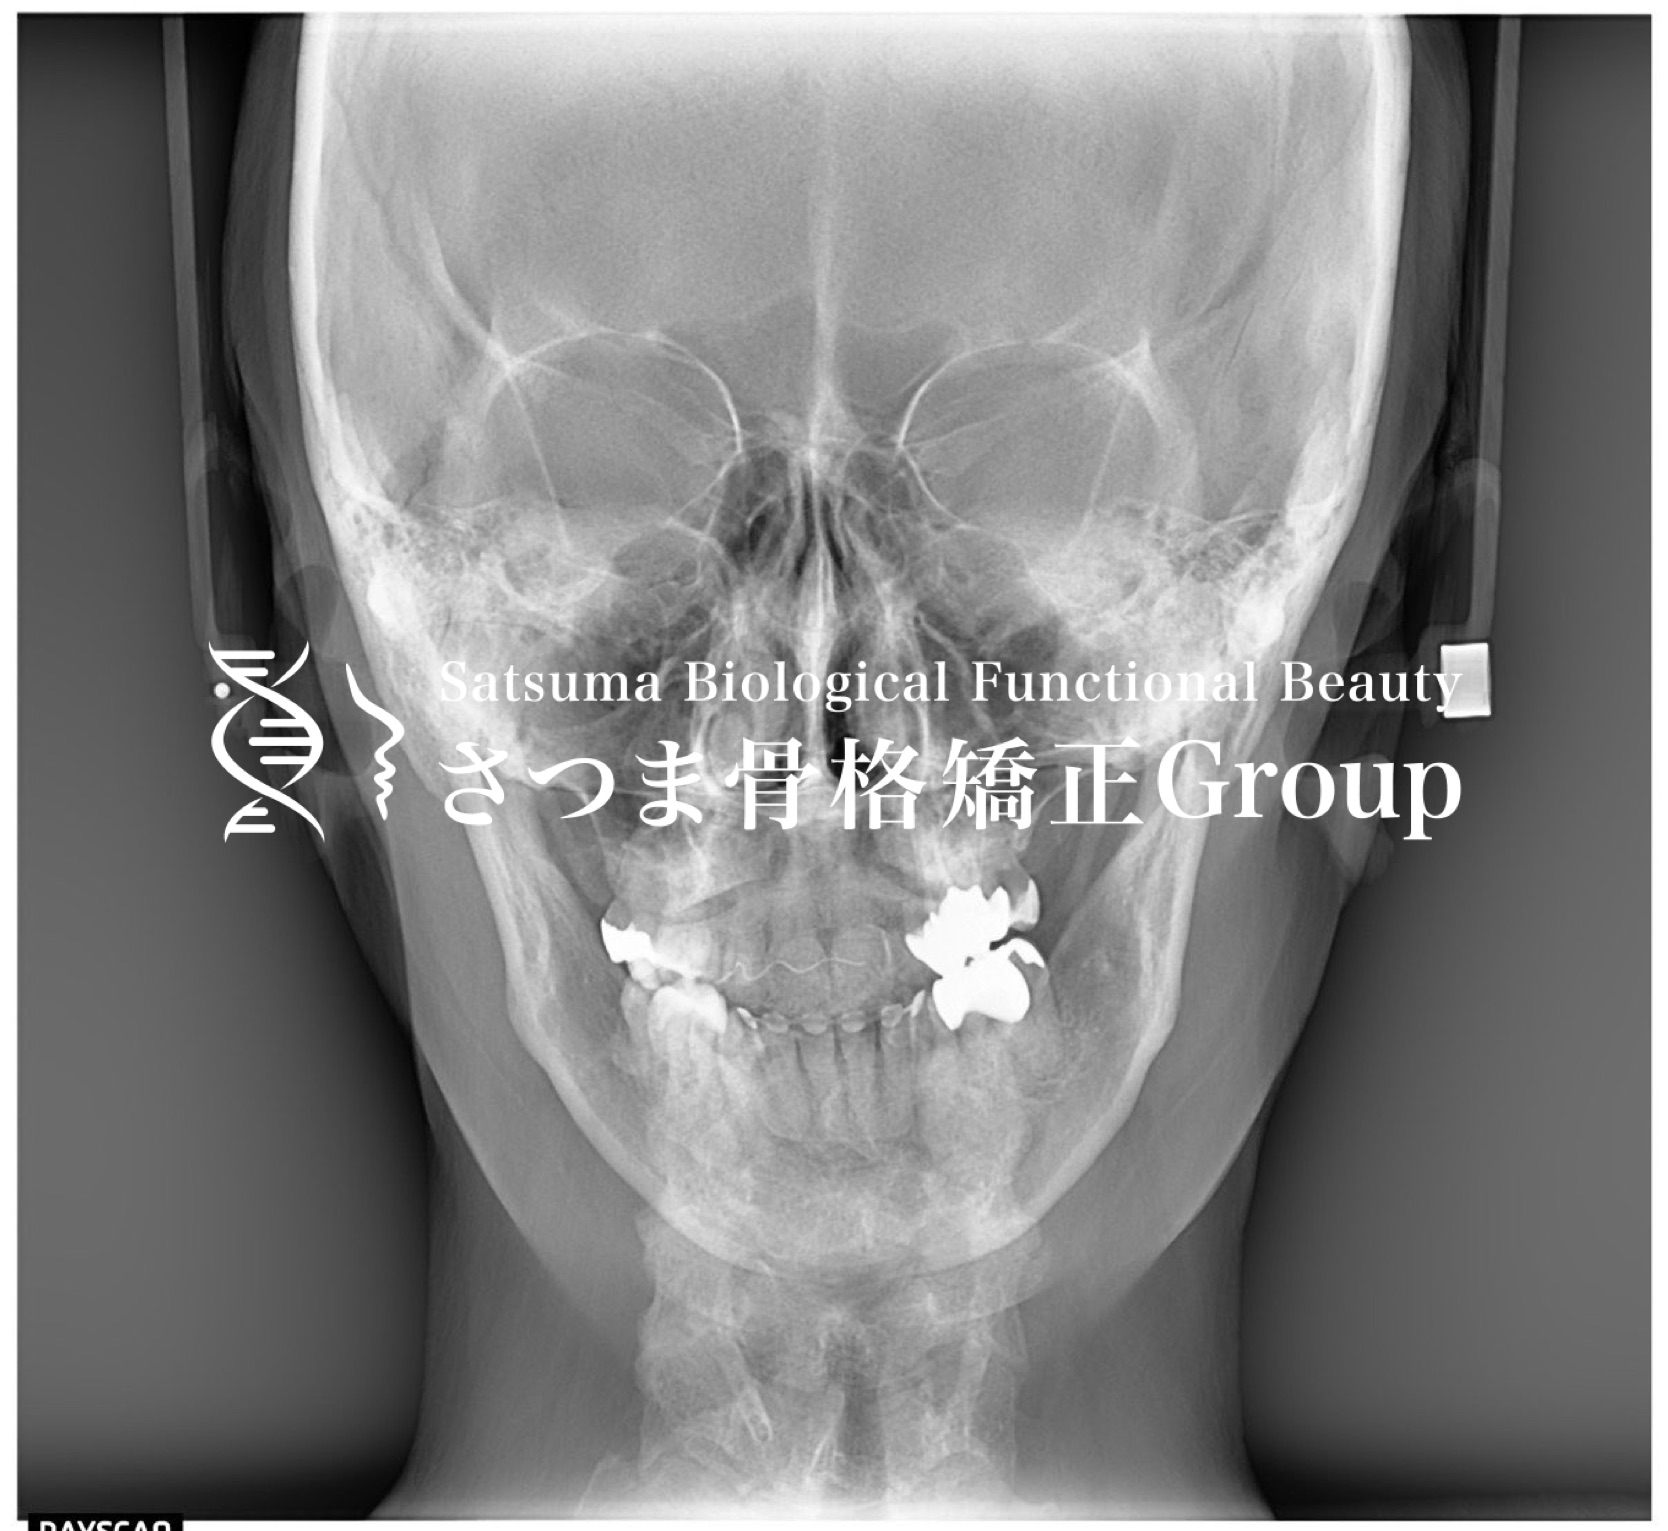

さつまではお顔の分析にあたり、セファロスタンドを使っています。 さつまでは主に口腔内から顎位や軟部組織に働きかけるお顔の施術を行いますので、まず通常の撮影した画像を参考に外形的な特徴を見ています。 バランスの良い美しいお